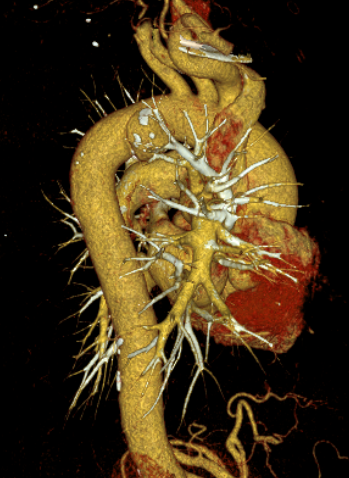

患者乔先生(化名)在查体时意外发现胸主动脉瘤,经主动脉CTA检查确诊后,医生发现其瘤体局部已出现先兆破裂迹象,随时可能发生破裂出血。要知道,胸主动脉是人体最大的动脉血管,堪称生命“主干道”,而胸主动脉瘤就像“体内的不定时炸弹”,一旦破裂,死亡率极高,救治刻不容缓。

一切准备就绪后,手术在全身麻醉下正式开展。手术团队凭借精湛的技术,经患者右侧股动脉穿刺,精准置入导丝及导管,在数字减影血管造影(DSA)的实时引导下,将覆膜支架系统精准输送至主动脉瘤病变部位,确认位置无误后,精准释放支架。整个手术过程精准、高效,仅用半小时便圆满完成。术后即刻造影显示,动脉瘤被完全隔绝,主动脉血流恢复通畅,无内漏、支架移位等异常情况,手术效果达到预期。

胸主动脉瘤并非肿瘤,而是主动脉壁因各种原因(如动脉粥样硬化、高血压等)发生局部或弥漫性扩张,形成“瘤样”膨出。它起病隐匿,早期常无症状,一旦破裂,死亡率极高。介入下覆膜支架植入术是目前治疗主动脉瘤的主流微创技术。与传统开胸手术相比,该技术具有创伤小、出血少、恢复快、并发症低等显著优势,尤其适合高龄、基础疾病多、无法耐受开放手术的患者。(通讯员 续宁)